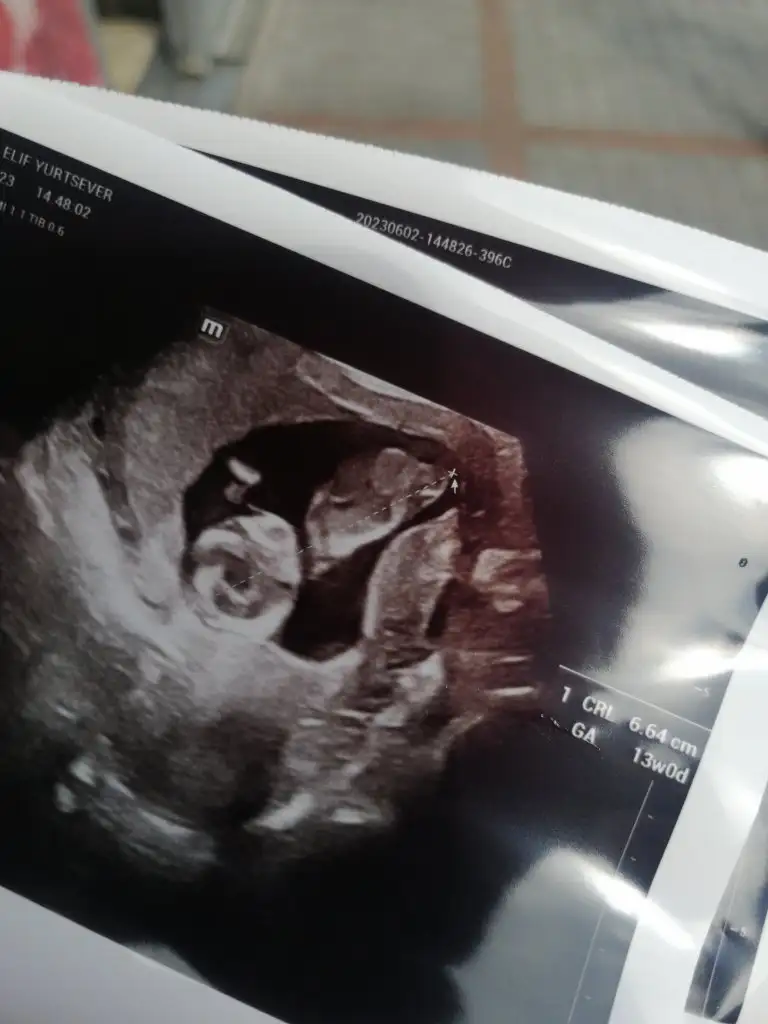

Merhaba banada yorumda bulunabilirmisiniz

Eklentiler

• IMG-20230602-WA0035.webp

IMG-20230602-WA0035.webp

20,3 KB · Görüntüleme: 45

• IMG-20230602-WA0029.webp

IMG-20230602-WA0029.webp

23,1 KB · Görüntüleme: 57

• IMG-20230602-WA0017.webp

IMG-20230602-WA0017.webp

22,9 KB · Görüntüleme: 67